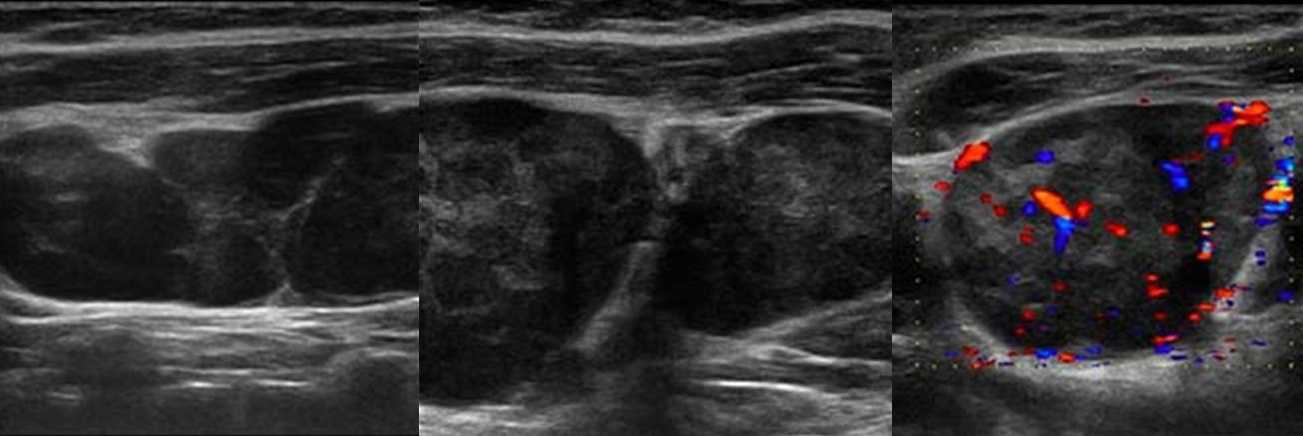

10 признаков злокачественного лимфоузла на УЗИ

- Большие размеры, более 10 мм;

- Округлая форма, соотношение длинного и короткого размера (Д/К) <2;

- Эхогенность диффузно или локально понижена вплоть до анэхогенной;

- Концентрическое или эксцентрическое расширение коркового слоя;

- Гиперэхогенный центральный рубчик истончен или отсутствует;

- Неоднородная эхоструктура за счет гиперэхогенных кальцинатов и/или анэхогенных зон некроза;

- Неровный и размытый контур, когда клетки опухоли прорастают капсулу;

- Часто образуют крупные конгломераты;

- Кровоток дефективный — сосуды смещены, хаотично организованы, диаметр не уменьшается по направлению к капсуле, выраженный подкапсульный кровоток, аваскулярные зоны и др;

- Высокий индекс резистентности (RI >0,8) и пульсации (PI >1,5).

Рисунок. На УЗИ лимфоаденопатия с эхо-признаками злокачественного процесса: увеличенный (28х16 мм) лимфоузел, округлой формы (Д/К <2), гипоэхогенный без центрального рубчика; определяется подкапсульный кровоток, диаметр сосудов не уменьшается по направлению к капсуле, RI 0,88.

Рисунок. Мужчина 63-х лет обнаружил «опухоль» на шее: растет медленно без боли и лихорадки. На УЗИ в районе кивательной мышцы определяется группа резко гипоэхогенных лимфоузлов без центрального рубчика, размер 10-20 мм; часть лимфоузлов округлые; встречаются лимфоузлы с резко усиленным кровотоком. Заключение по результатам биопсии: Лимфома.

Рисунок. Женщина 32-х лет с «опухолью» на шее. На УЗИ в левой надключичной области определяются один большой и несколько маленьких гипоэхогенных лимфоузлов, округлой формы, центральный гиперэхогенный рубчик тонкий; кровоток заметно усилен, сосуды расположены хаотично, диаметр не уменьшается по направлению к капсуле, выраженный подкапсульный кровоток. В левой подвздошной ямке видно «сэндвич» — конгломерат из увеличенных гипоэхогенных лимфоузлов, между которыми залегают сосуды брыжейки. Заключение: Лимфоаденопатия с эхо-признаками злокачественного процесса. Рекомендована биопсия измененных лимфоузлов.